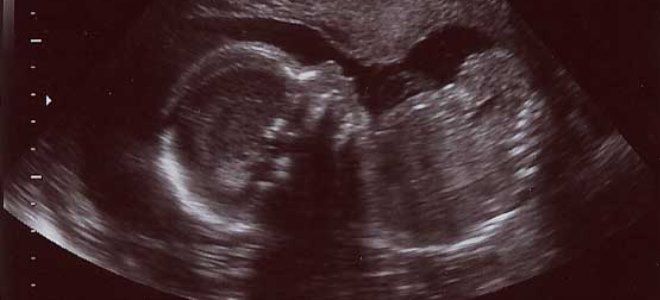

УЗИ на 22 неделе беременности

УЗИ на 22-й неделе беременности предоставляет возможность оценить состояние плода и развитие его внутренних органов. На этом этапе процедура не является стандартной, поэтому проводится только при наличии конкретных показаний или в случае поздней регистрации женщины на учет. Наилучшим временем для проведения УЗИ считается период с 16 до 20 недель гестации. Во время исследования специалисты определяют ключевые параметры физического развития ребенка, местоположение и состояние плаценты, а также фиксируют возможные отклонения в внутриутробном развитии.

На 22 неделе беременности в матке еще достаточно пространства, и плод может свободно двигаться, совершая перевороты и кувырки. На этом этапе беременности малыш может менять свое положение несколько раз в день, поэтому врачи не обращают особого внимания на предлежание в столь ранние сроки. Тем не менее, для того чтобы убедиться в изменении положения ребенка, ультразвуковое исследование обязательно проводится на 28-30 неделях.